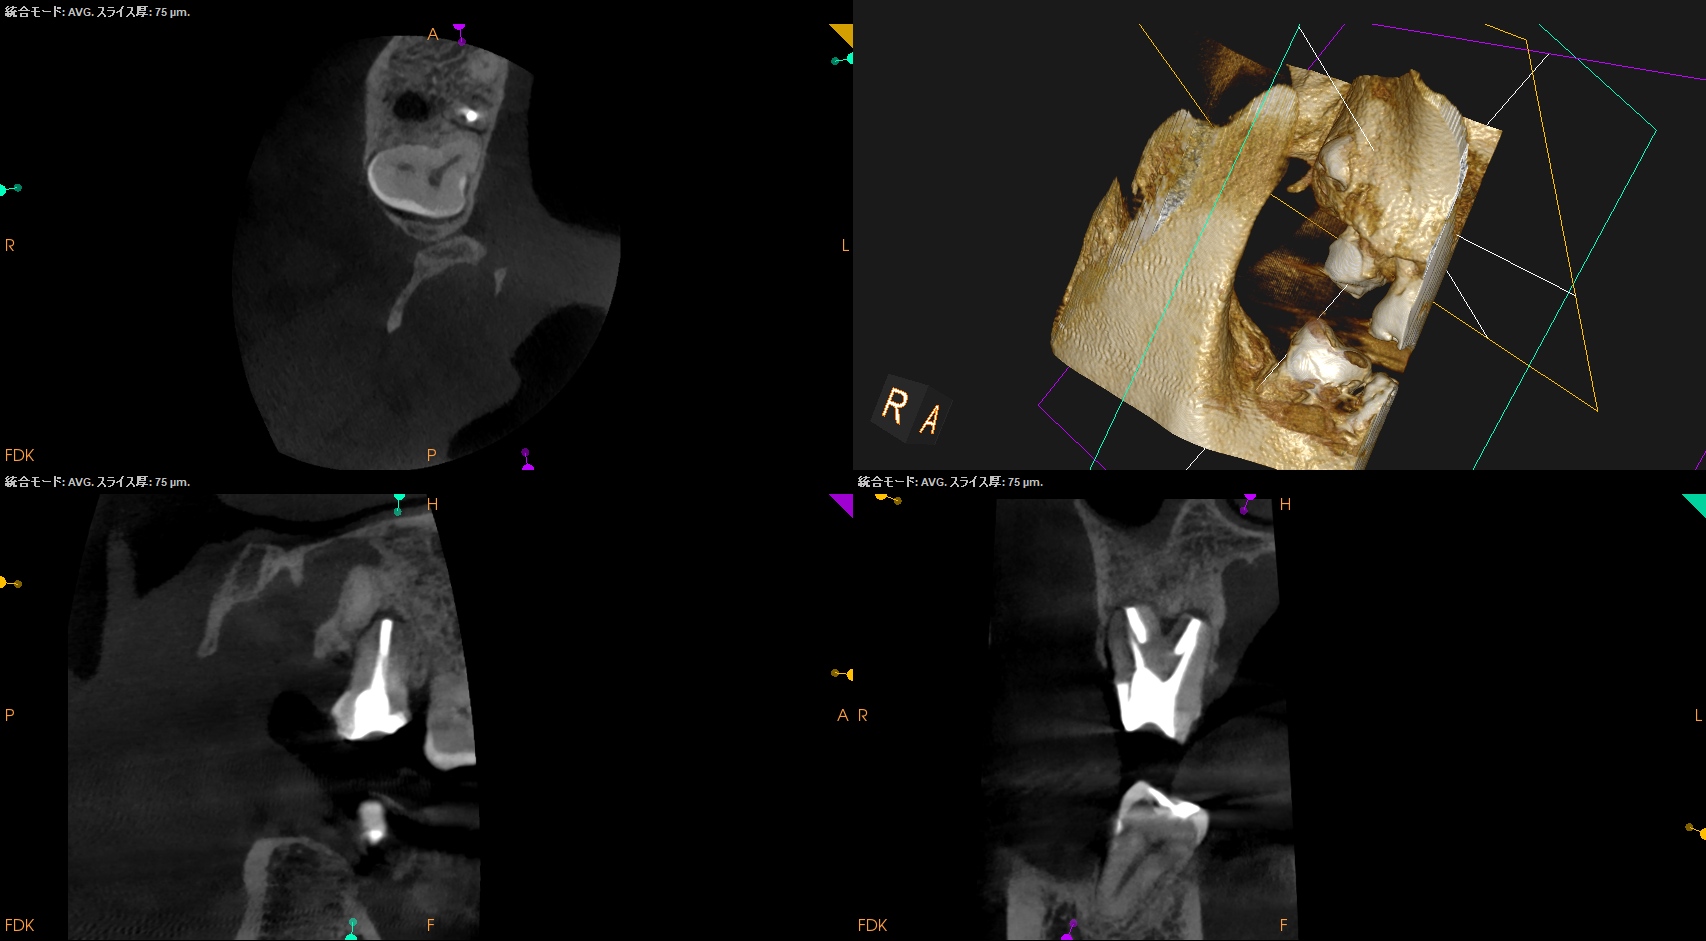

この1ヶ月後に経過観察で来院された。

#2 Intentional Replantation 1M recall(2026.1.28)

問題はないだろう。

次回は半年後である。

またその模様をお伝えしたい。